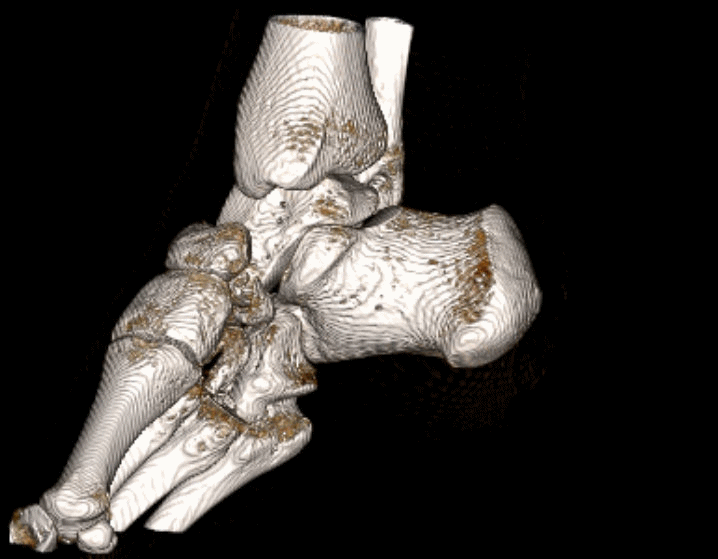

Kriplíci, úrazy, zranění a simulace